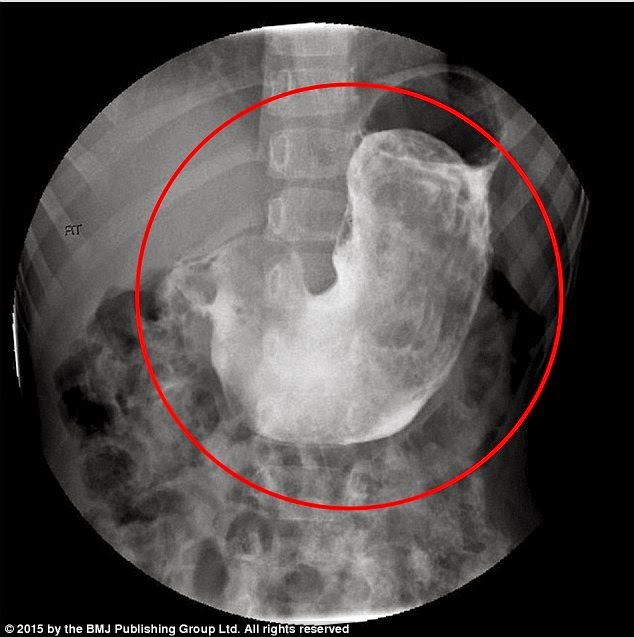

Όταν οι γιατροί εξέτασαν το κοριτσάκι, εντόπισαν μια μεγάλη, συμπαγή μάζα στην κοιλιά της. Οι απεικονιστικές εξετάσεις επιβεβαίωσαν την ύπαρξη της μάζας τριχών στο στομάχι της.

Η 5χρονη από την Αυστραλία υποβλήθηκε σε επείγουσα χειρουργική επέμβαση, κατά την οποία αφαιρέθηκε μάζα 125 γραμμαρίων (περίπου όσο ένα μήλο) από το στομάχι της. Ήταν σε θέση να φάει μετά την επέμβαση και αναρρώνει, ενώ ακολουθεί συμπεριφορική θεραπεία ώστε να αντιμετωπίσει την τριχοτιλλομανία.